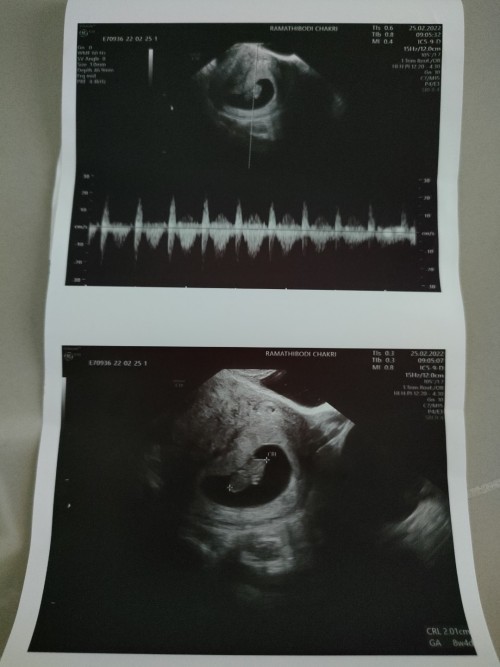

เราท้องได้9weekแต่ไปซาวกับไม่เจอตัวน้องคะซาวทั้งหน้าท้องและทางช่องคลอดตอนนี้เครียดมากการคัดเต้าก็ยังปกติคะมีเหม็นกลิ่นอาหารบ้างตอนนี้จิตตกเข้าออกตามเว็บหาข้อมูลทำใจไม่ได้เลยคะแม่ท่านไหนเป็นแบบนี้บ้างคะ

9 week #ไปตรวจมาวันนี้หมอบอกหัวใจน้องไม่เต้นแล้ว แม่ร้องไห้หนักมาก งง หนักมาก ว่าจะไปตรวจอีกที

ชาวด์ตอน 9วีก หมอบอกท้องลมค่ะ ตอนนี้รอวันนัดไปเอาถุงตั้งครรภ์ออก เป็นกำลังใจให้ค่ะ🥰🥰

ซาวด์ทางช่องคลอด9wคะ มีเสียงหัวใจเต้นคะดีใจมากแต่มีถุงน้ำในรังไข่คุณแม่กังกลมากคะ